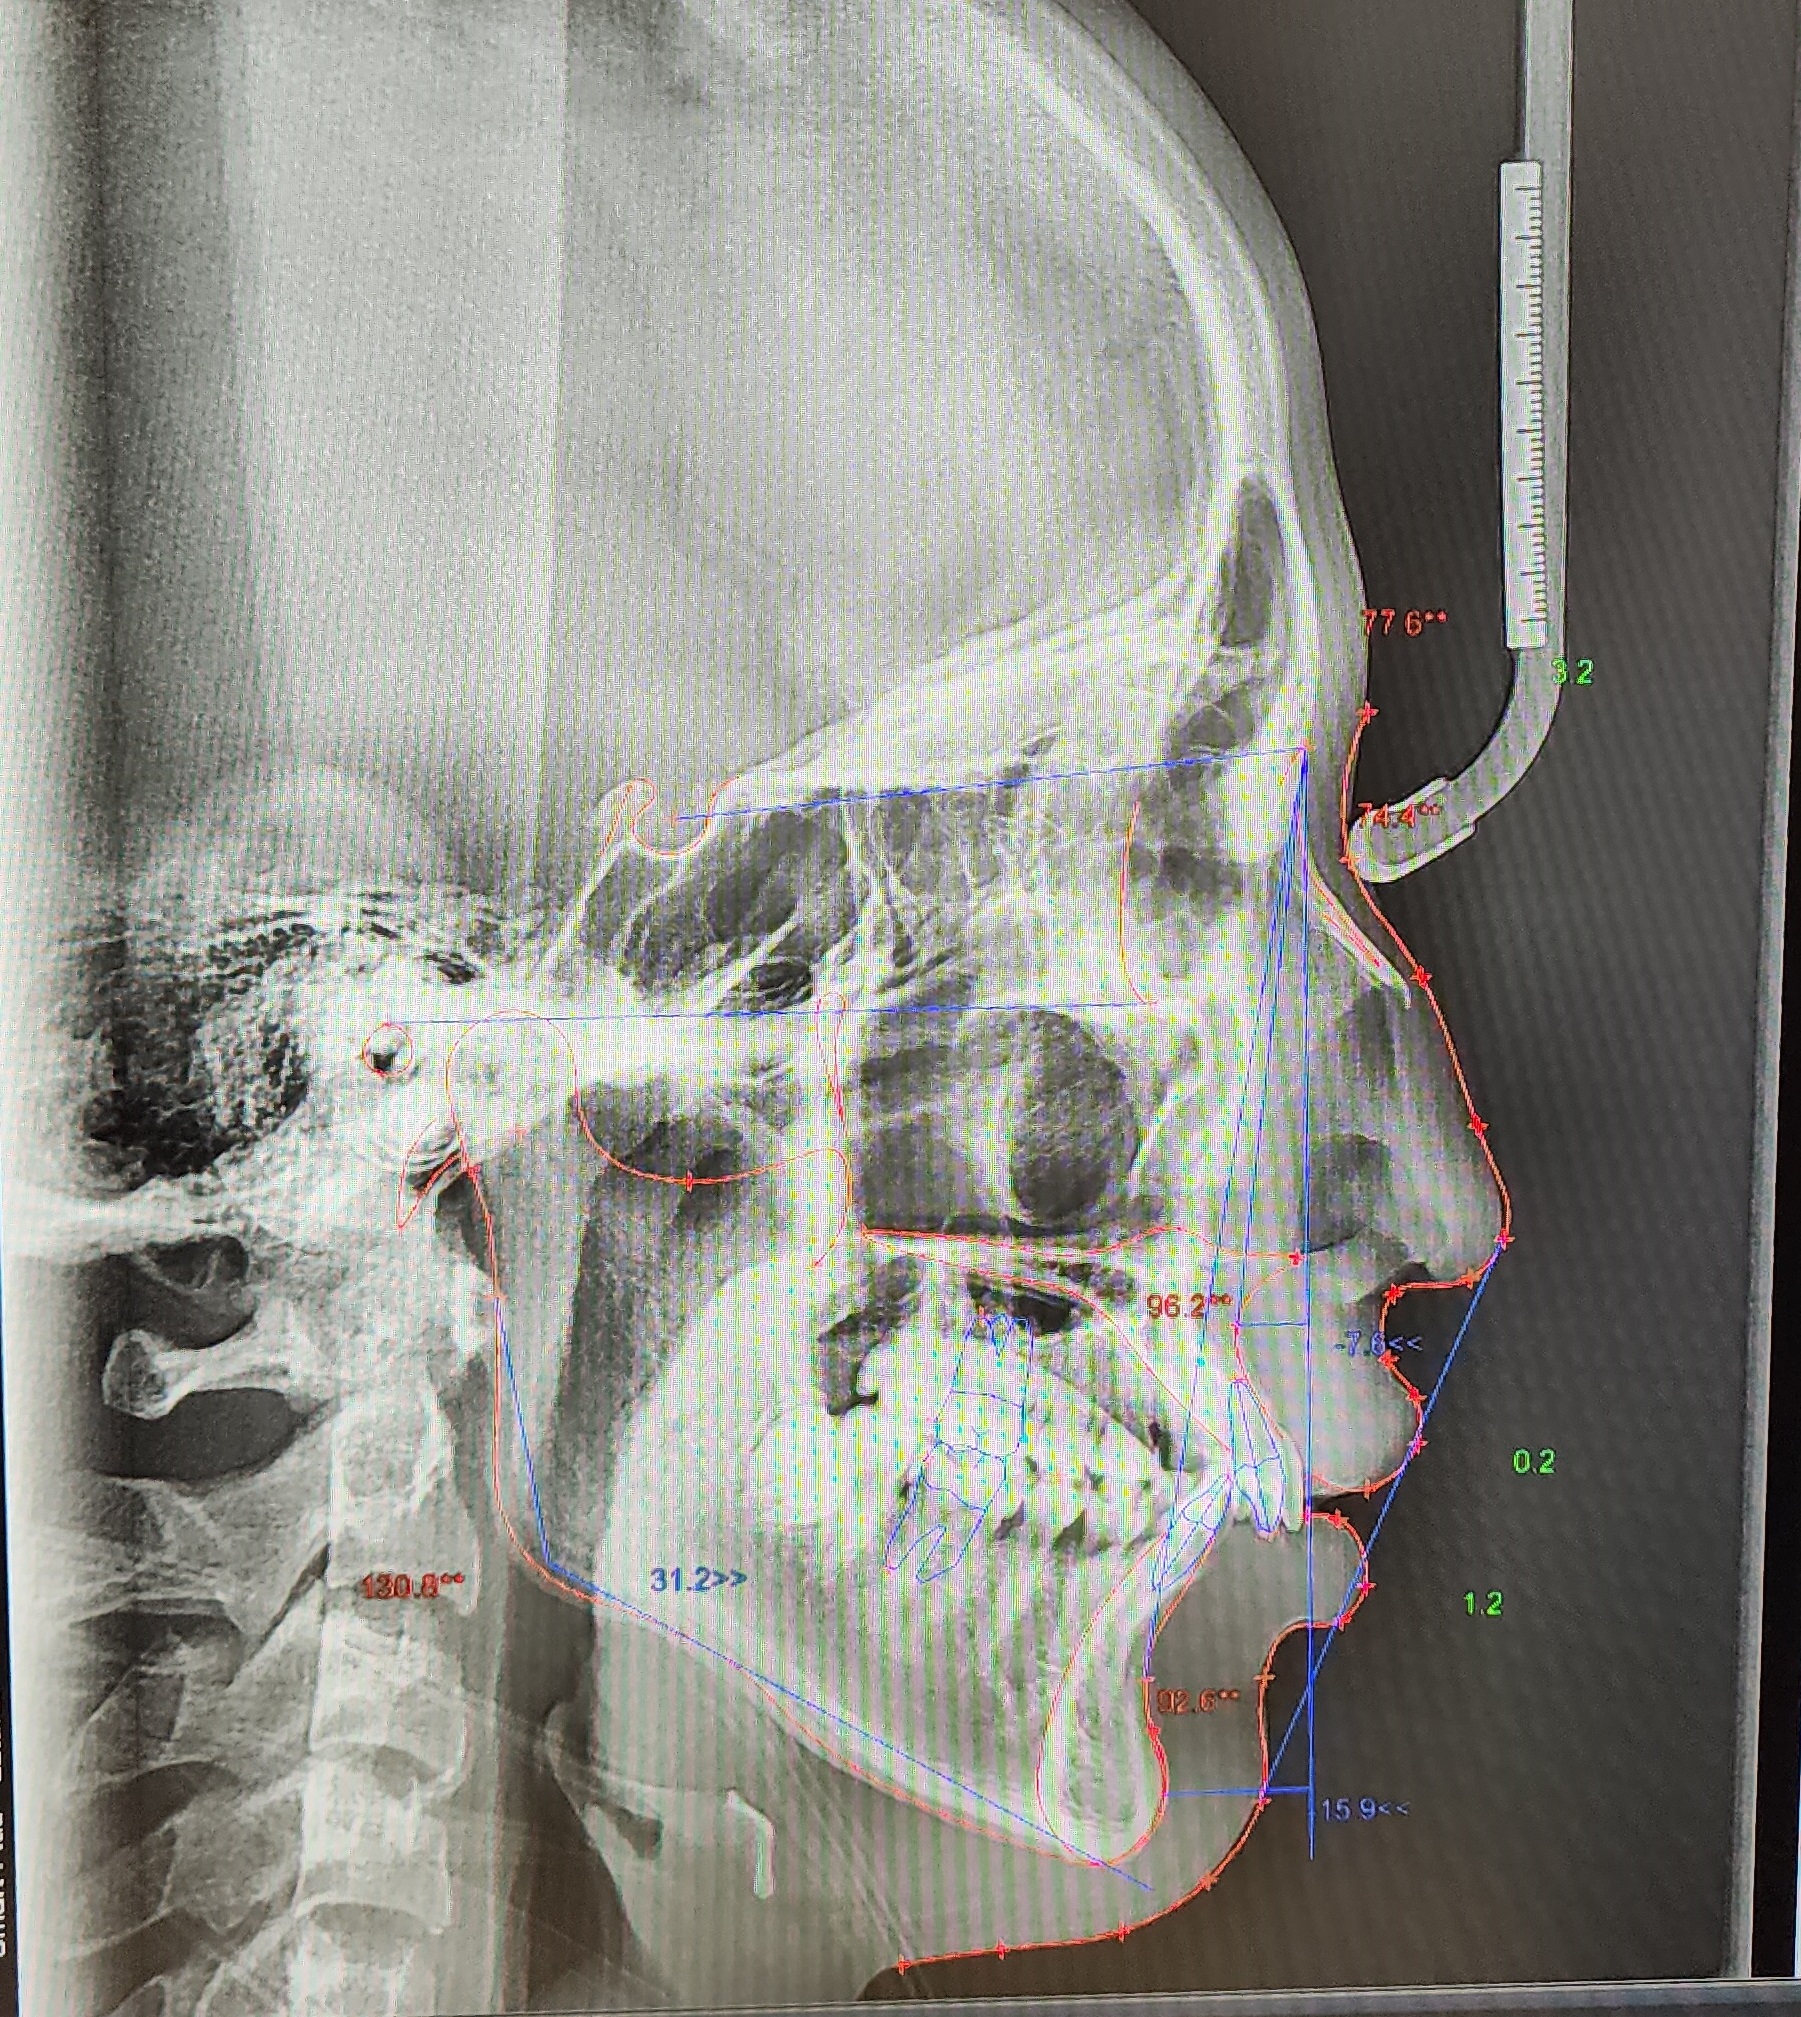

전체적인 치아상태 및 배열 안면윤곽 상태 등 정밀검사를 실시하였으며 아들이 고등학생이어서 성장판 검사는 별도로 하지 않았습니다.

정밀검사비용은 150,000원이 들었으며 전체교정비용은 590만 원으로 결정이 되었습니다. 치료방법에 따라 다르기 때문에 참고만 하시길 바랍니다.

● 검사결과 내용

치아뿌리상태는 좋고 어금니 가위교합(3개월정도)을 먼저 하고 어느 정도 진행이 되면 전체브라켓을 설치 후 과개교합(2개월정도) 교정을 실시한후 2차 정밀검사를 하고 발치여부를 판단하기로 하였습니다.

저는 상담 시 되도록이면 발치는 하지 않는 방향으로 한다고 말씀드렸고 다행히 2차 정밀검사 마친 후 발치 없이 전체교정을 시작할 수 있었습니다.

▼ 1차 정밀 검사 X-RAY

▼ 치아상태 및 얼굴 각도 치아 치수확인